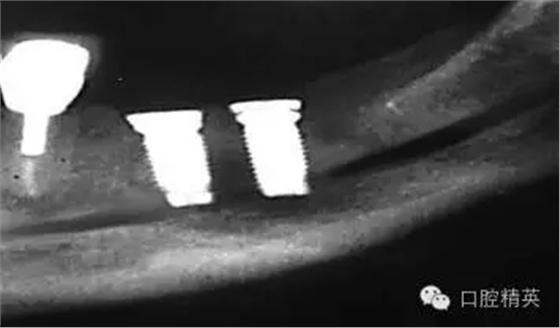

圖7a:6,7號牙種植體(3*15mm)折斷前,從物理學(xué)理論上講,種植體骨整合后,基臺螺絲和種植體相連接的支點處是受力時種植體最薄弱的位置。(a)可見6號牙種植體的折斷面,和7號牙種植體上的折裂線(b)。

圖7b:6,7號牙種植體折斷后。

圖7c,d:6,7號牙的回顧性模型分析顯示為了獲得滿意的美學(xué)效果牙冠不得不做的很長,從而形成較深的咬合關(guān)系。同時可見對頜牙磨耗嚴(yán)重,廣泛。

種植體折斷可能發(fā)生于種植體行使功能幾年后,也可能發(fā)生于早期。(圖7a,b)對于圖中這一病例,治療計劃是在對患者的咬合關(guān)系,未來修復(fù)體理化環(huán)境,患者咀嚼習(xí)慣等充分評估后制定的。種植體折斷后,對該病例進行了回顧性病因分析,上了頜架的模型揭示了過長的頜間距離,和嚴(yán)重、廣泛的對頜牙磨耗(圖7c,d)。對于這一病例,醫(yī)生仔細(xì)評估了所有可得到的回顧性診斷信息,和患者進一步討論交流后,提出了幾個診斷建議和一個過渡性治療方案,其中包括將固定修復(fù)改為鑄造可摘局部義齒。

考慮到取出種植體會造成很大的創(chuàng)傷,醫(yī)生提出了一個盡量避免增加創(chuàng)傷風(fēng)險的折中治療方案。治療為:嚴(yán)密縫合關(guān)閉6號,7號牙種植體周圍軟組織,將種植體埋入休眠。術(shù)后即刻戴入塑料過渡活動義齒,術(shù)區(qū)軟組織穩(wěn)定后進行鑄造可摘局部義齒修復(fù)。